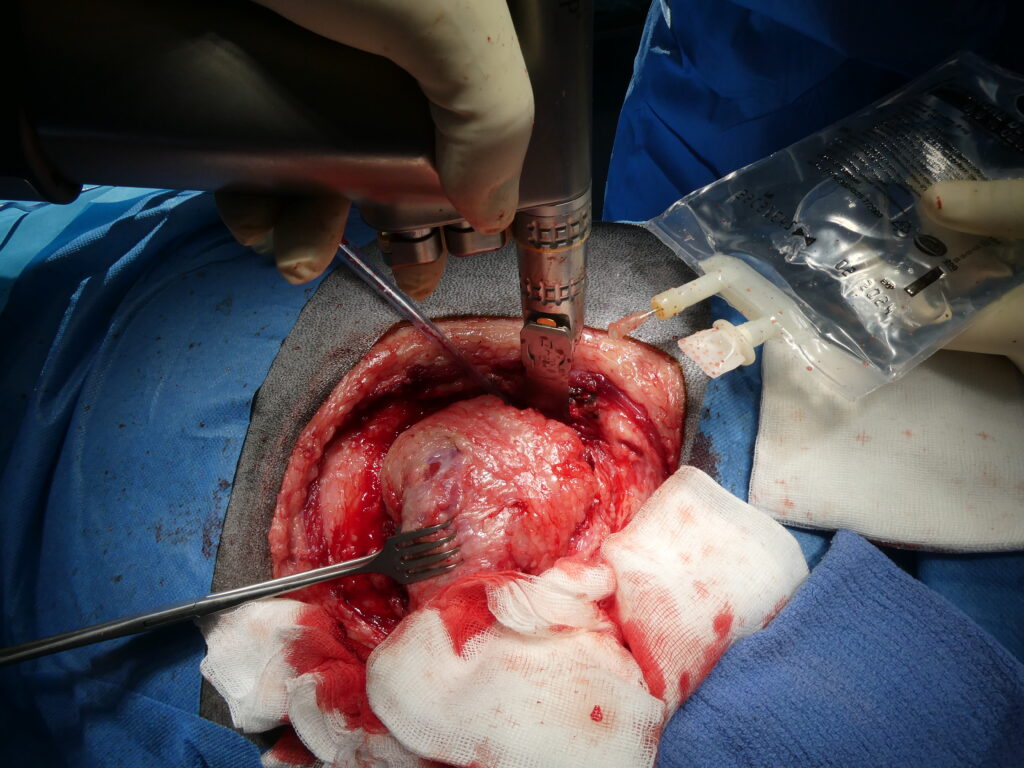

Traitement chirurgical de l’abcès par thoracotomie et épiplooplastie.

En haut à gauche, ouverture de l’abcès pulmonaire par thoracotomie intercostale en région caudale, avec ponction et aspiration initiale du contenu purulent, dans un contexte de dyspnée sévère liée à l’occupation d’environ la moitié de l’hémithorax gauche.

En haut au centre, aspect de la cavité de l’abcès après évacuation complète et nettoyage, mettant en évidence un espace résiduel important nécessitant un drainage durable.

En haut à droite, réalisation d’une laparotomie abdominale afin de prélever un segment d’épiploon destiné à être utilisé comme drain biologique.

En bas à gauche, tunnelisation sous-cutanée de l’épiploon entre la cavité abdominale et la cavité thoracique, permettant son transfert sans tension vers le site pulmonaire.

En bas au centre, mise en place de l’épiploon au sein de la cavité de l’abcès, avec marsupialisation et fixation, afin d’assurer un drainage continu et un apport local en cellules immunitaires.

En bas à droite, fermeture finale du thorax et de l’abdomen après mise en place de l’épiploon, illustrant l’utilisation de ce tissu comme drain naturel particulièrement efficace, favorisant le contrôle de l’infection, la résorption du pus, l’apport vasculaire et la cicatrisation en chirurgie thoracique.